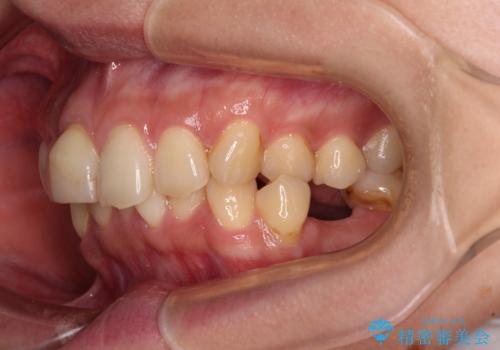

デコボコと乳歯の欠損 ワイヤー矯正とインプラント補綴治療

- 全体的なデコボコと左下乳歯部の欠損を気にして来院された患者様です。

乳歯が抜け落ちた後の後続永久歯が欠損しているため、スペースが残っておりました。

口元の突出感を気にしているのであれば欠損スペースを利用して抜歯矯正を行うことも可能ですが、横顔の印象はスッキリとしている状態であったため、矯正治療でスペースを閉じきることは不可能と判断し、インプラントによる補綴治療を行うこととしました。

第二小臼歯の欠損によるが乳歯残存や欠損が多く、この乳歯は後続永久歯に比べて幅が非常に大きいため、教聖地料によるスペースクローズが難しいことが一般的です。